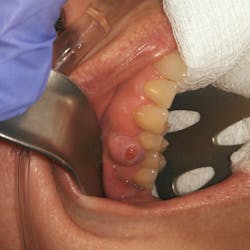

A 50-year-old female presented for a new-patient exam upon the recommendation of her general practitioner. Her chief complaint: “My doctor said that I have an infection on one of my top right teeth.” She pointed to a raised tissue mass between teeth nos. 4 and 5.

Clinical assessment revealed a 6 mm pink, raised, firm mass of osseous tissue measuring 12x12 mm. It was not tender to palpation and did not bleed easily when manipulated (figures 1 and 2). Radiographic assessment was within normal limits (figure 3).